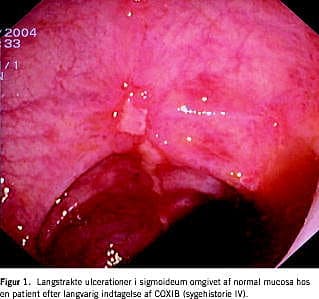

IV. En 48-årig kvinde med et tidligere mangeårigt NSAID-forbrug mod slidgigt blev i fire år behandlet med celecoxib 400 mg daglig. Hun blev indlagt med akut indsættende, stærke abdominalsmerter samt frisk blødning og koagler per rectum. Ved en koloskopi sås der striktur på grundlag af langstrakte ulcerationer i sigmoideum omgivet af normal mucosa (Figur 1). Histologien viste inflammation med kirtelhenfald og ulcerationer med fibrinbelægninger, fibrose i lamina propria og ingen kryptabcesser eller granulomer. Efter seponering af celecoxib forsvandt patientens gener og de endoskopiske forandringer.

Sygehistorierne tyder på en sammenhæng mellem indtag af COXIBs og sygdom i colon. Læsionerne i sygehistorie 4 og 5 ligner tidligere beskrevne læsioner efter langvarig indtagelse af NSAID [1, 2] og kan forveksles med Crohns læsioner (Figur 1). Perforationen hos patienten i den første sygehistorie skete efter kort tids behandling med refecoxib. Det tidsmæssige sammentræf og fravær af anden forklaring tyder på en sammenhæng. Isolerede ulcerationer ses ikke sjældent hos patienter med en ilioanal pouch og iliorektal anastomose, men sene perforationer er usædvanlige. COXIBs hæmmer angiogenesen og dermed helingen. NSAID og COXIBs indgår rutinemæssigt i den postoperative smertebehandling, og det vides ikke, hvorvidt disse øger incidensen af anastomoselækage og postoperativ blødning.